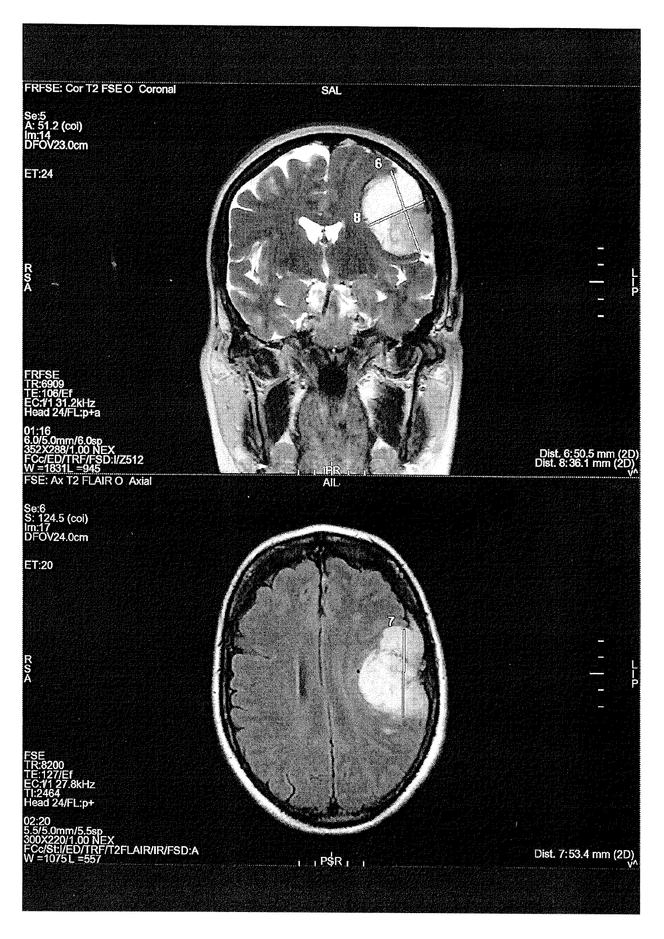

Une IRM montrant un méningiome provoqué chez une victime par la prise d’un progestatif. DOCUMENT LE MONDE Un nouveau front judiciaire s’ouvre dans l’affaire de l’Androcur,cette pilule miracle prescrite pendant des années pour traiter l’endométriose,l’acné,la chute de cheveux ou encore comme moyen de contraception,mais à l’origine de tumeurs du cerveau (méningiomes) chez des centaines de femmes. Selon les informations du Monde,une plainte contre X a été déposée mardi 5 novembre devant le tribunal judiciaire de Paris par l’Amaeva,l’association qui regroupe les victimes de l’Androcur et des autres traitements hormonaux dérivés de la progestérone (Lutényl,Lutéran…). Elle vise cinq infractions pénales : administration de substance nuisible,atteinte involontaire à l’intégrité de la personne,mise en danger d’autrui,non-signalement d’effet indésirable,tromperie aggravée.